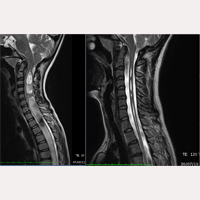

مرض الجنف أو السكوليــوز مجهــولة الــسبــب

إبتداءا من ٢٠ أكتوبر ١٩٩٣ حتى نوفمبر ٢٠١٦ تم التدخل جراحيا بإجراء عملية قطع الفيلوم ترمينالي، بواسطة تطبيق النظام الطبي الفيلوم سيستم®، على أزيد من ١٠٠٠ مريض مصاب بمرض الفيلوم و /أو متلازمة الجر العصبي مع متلازمة أرنولد كيارى النوع الأول، تكهف النخاع و الجنف، و ذلك في تركيبات مختلفة من التشخيص. في معضم الحالات تم التوصل الى تطورات إيجابية مرضية، إلا في خمسة منها ذي مضاعفات بسيطة